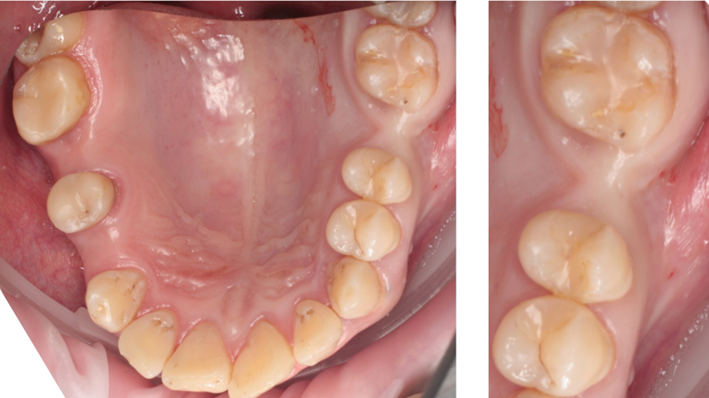

Clinical case: Ridge splitting technique using SmarThor + AnyRidge as expander

- Courtesy of Dr.Kwang-Bum Park, Korea -

AnyRidge, ridge splitting, GBR, Dr. Kwang-Bum Park, mandibular posterior, SmartThor, Mega-Oss, thin ridge, bone regeneration

Products:

AnyRidge implant system. SmarThor, Mega-Oss